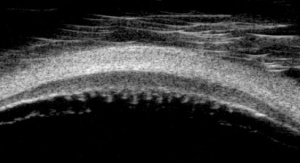

Ultrasound Biomicroscopy (UBM) is a technique primarily used for imaging of the anterior segment (AS) of the eye. It was first introduced in the early 1990’s by Foster and Pavlin as a way to obtain cross-sections of the eye at microscopic resolution.[1] Compared to regular ultrasound modalities such as A-scan or B scan (10 MHz), UBM uses a much higher frequency transducer (35-100 MHz).[2] This results in resolutions up to 20um axially and 50um laterally, and depth of tissue penetration is 4-5mm. UBM can be used for imaging much of the anatomy of the anterior segment, as well as associated pathologies, including angle closure glaucoma, ciliary body cysts, neoplasms, and angle trauma.

Further, UBM is frequently used in research to better understand the angle and can be used for qualitative analysis of the anterior chamber angle (ACA). Analysis and interpretation of images begins with identification of the scleral spur, a protrusion of the sclera into the anterior chamber that attaches anteriorly to the trabecular meshwork. UBM can describe the presence of angle closure glaucoma, which is indicated by irido-corneal contact anterior to the scleral spur. It can also distinguish between different types of angle closure, including pupillary block, plateau iris and lens-related.[6]